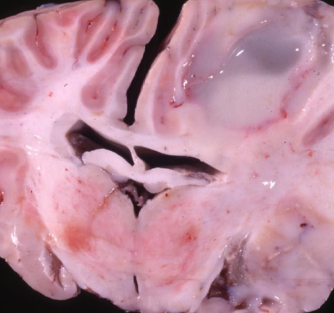

What is this in a goat?

Abscess